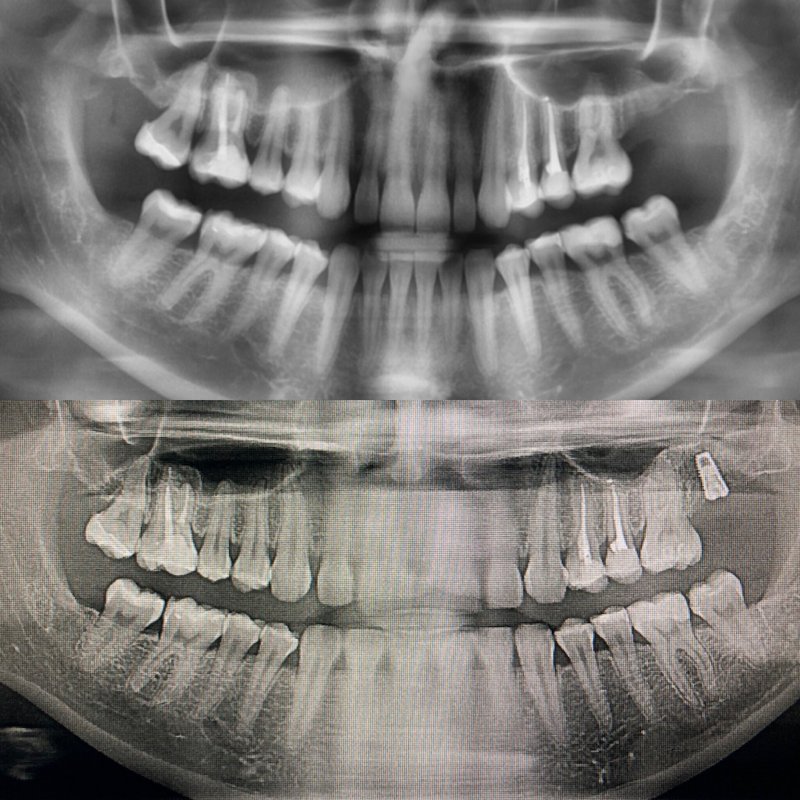

Медицинские Исследования: Кортикальная Пластинка на ОПТГ